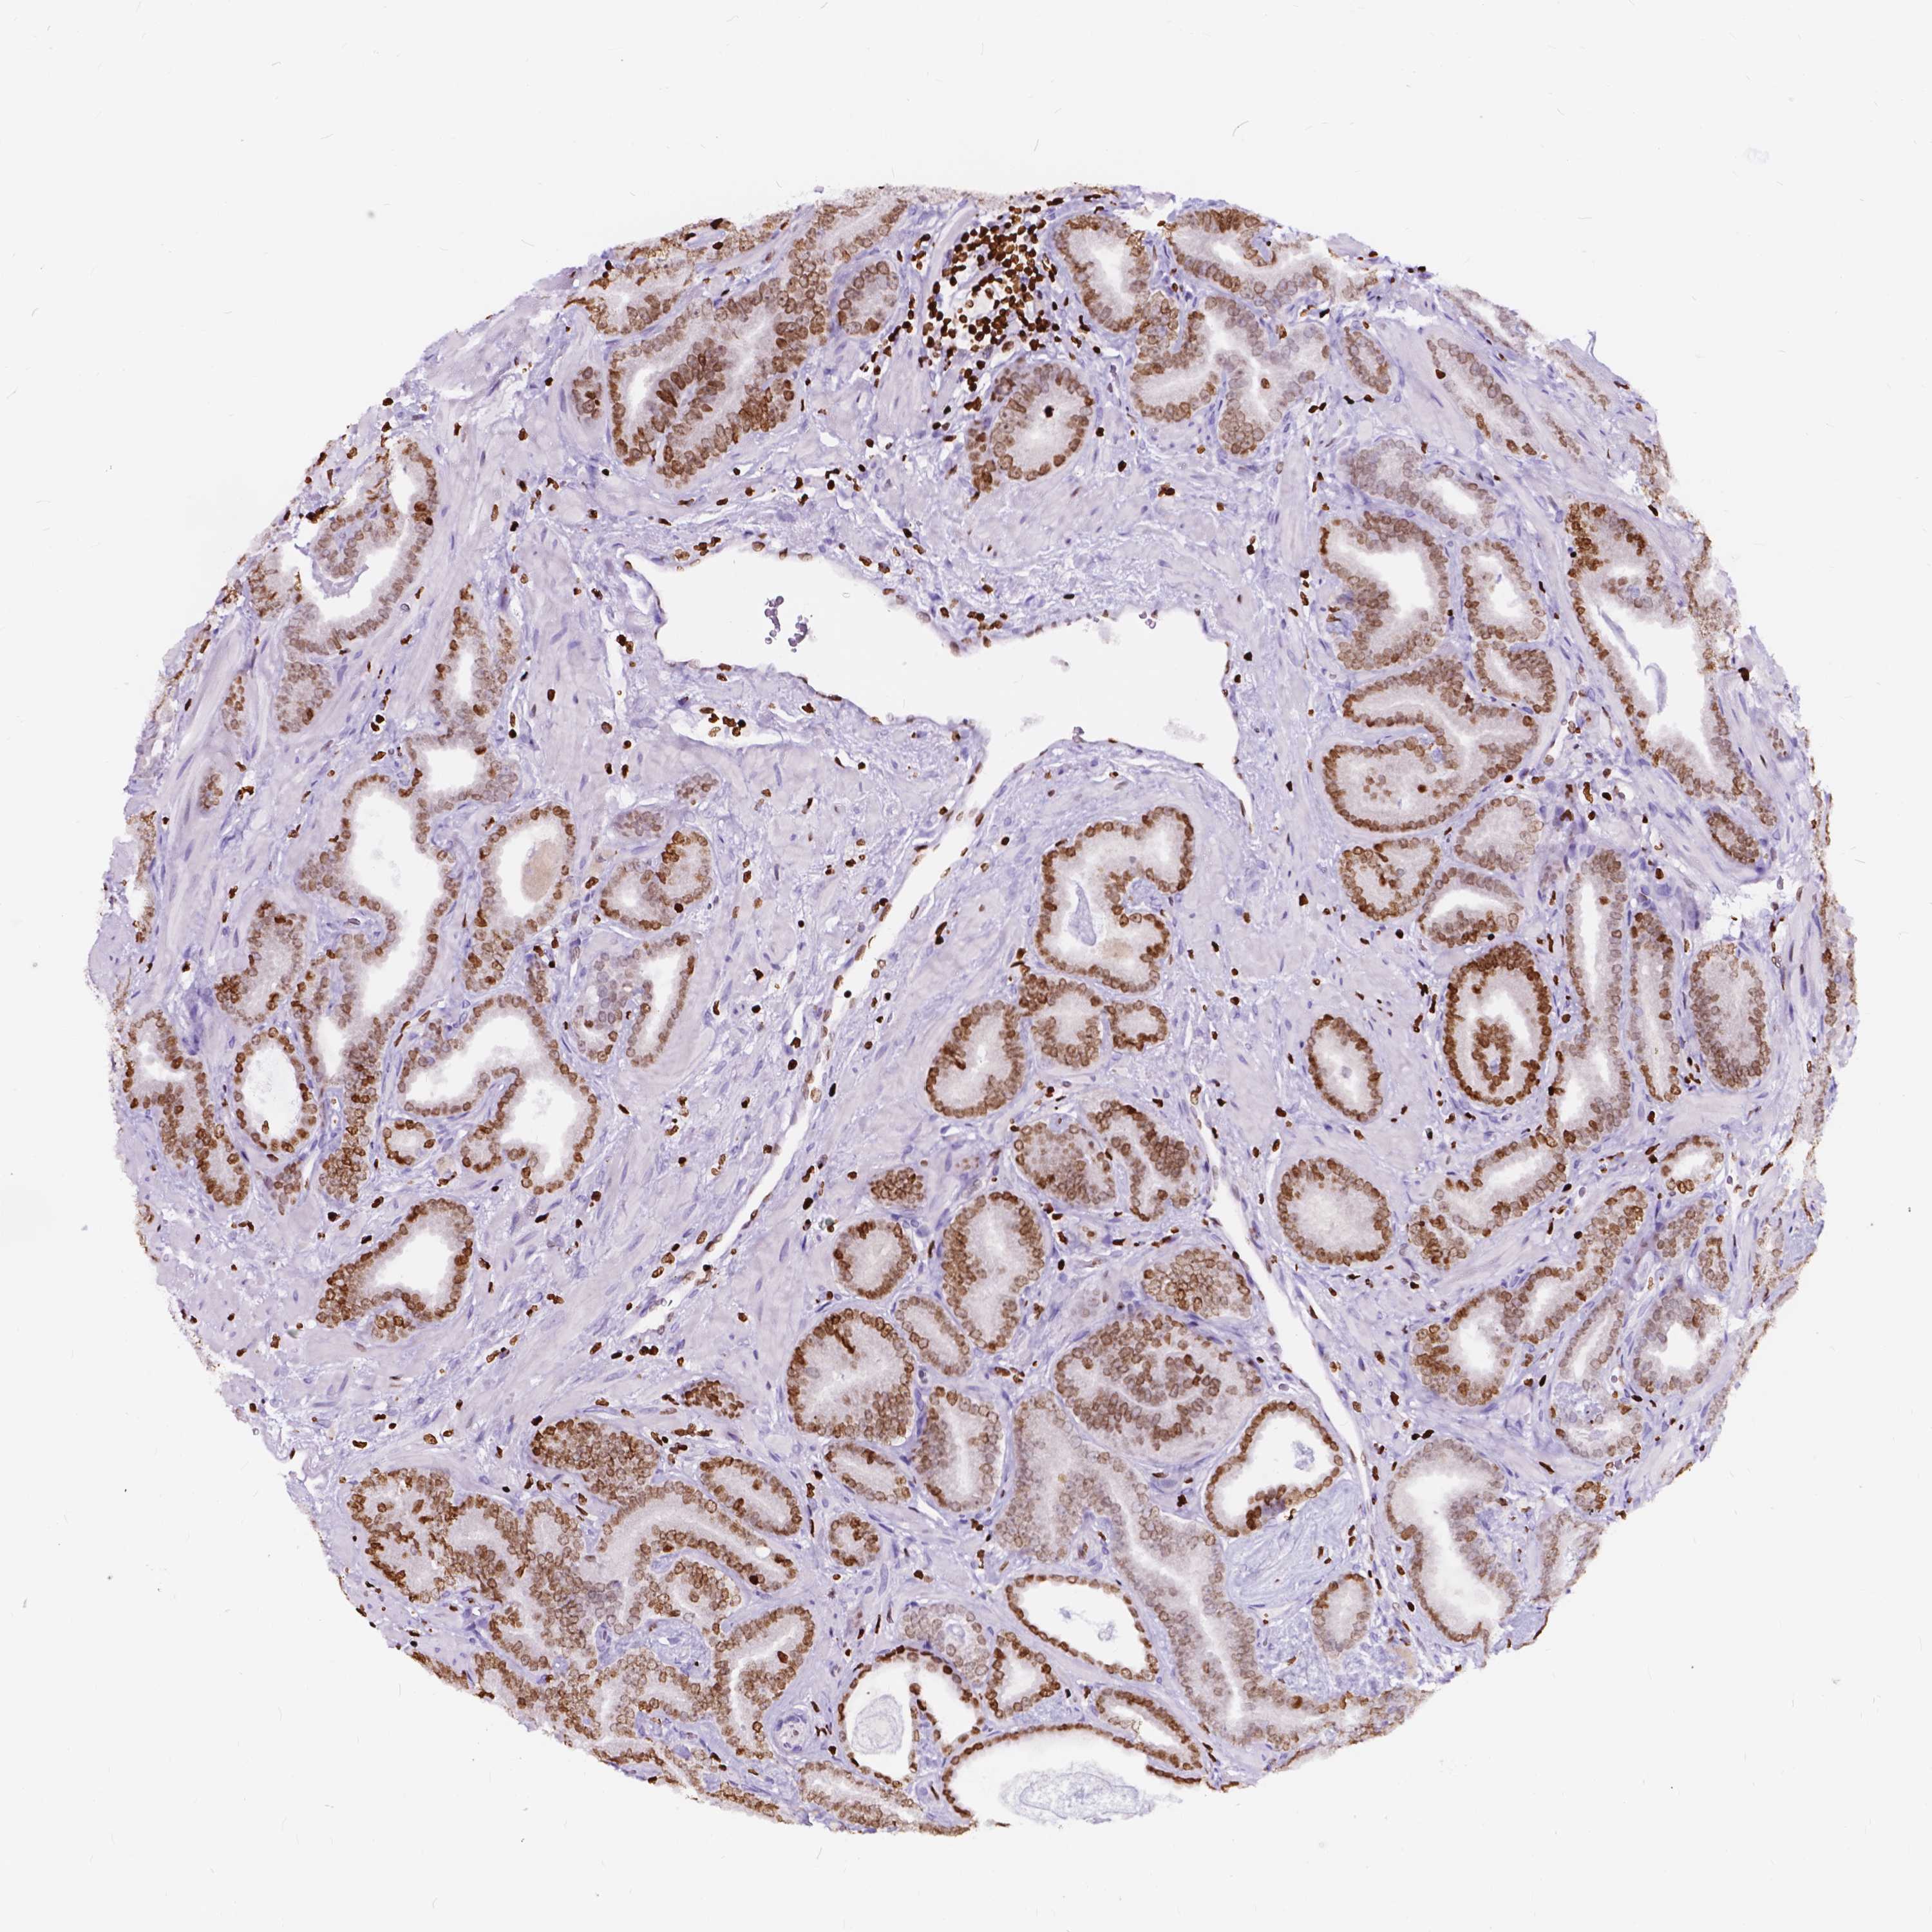

PROSTATE CANCER - Protein expressioni

A mouse-over function shows sample information and annotation data. Click on an image to view it in a full screen mode. Samples can be filtered based on level of antibody staining by selecting one or several of the following categories: high, medium, low and not detected. The assay and annotation is described here.

Antibody stainingi

Antibody staining in the annotated cell types in the current human tissue is reported as not detected, low, medium, or high, based on conventional immunohistochemistry profiling in selected tissues. This score is based on the combination of the staining intensity and fraction of stained cells.

Each image is clickable and will lead to virtual microscopy that enables deeper exploration of all samples and also displays staining intensity scores, fraction scores and subcellular localization as well as patient and tissue information for each sample.

Antibody HPA069037

Staining

High

Medium

Low

Not detected

Intensity

Strong

Moderate

Weak

Negative

Quantity

>75%

75%-25%

<25%

None

Location

Nuclear

Cytoplasmic/membranous

Cytoplasmic/membranous,nuclear

Adenocarcinoma, High grade

Adenocarcinoma, NOS

Adenocarcinoma, Low grade